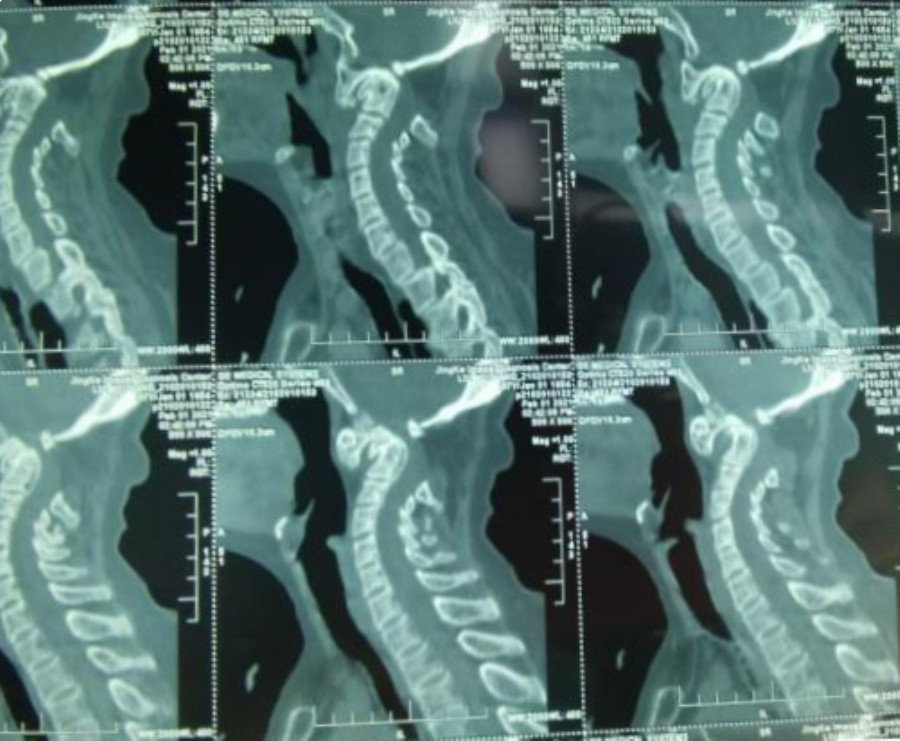

患者67岁,4个月前无明显诱因出现四肢麻木僵硬无力,不能自行站立、行走,曾行针灸治疗效果不明显,且症状逐渐加重。在进一步寻求诊疗的过程中,于今年年初慕名来91直播 找到颈椎外科张沛主任就诊。张主任结合颅脑和颈椎的相关检查,经阅片查体后诊断为“1、寰枢椎脱位;2、先天性齿状突发育不良;3、慢性脊髓病”而收入住院治疗。

术前颈椎CT